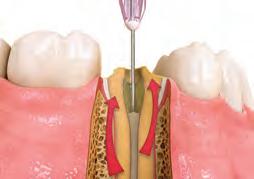

Reduce cross-contamination and need for sterilizing by loading unit dose syringe directly from the IndiSpense™ syringe.

2. Give firm air/water spray to remove residual coagulum and to test for profound hemostasis. If bleeding continues, repeat.

3. After complete hemostasis has been attained, excellent retraction is achieved using Ultrapak™ knitted cord placed with the Ultrapak™ packer.